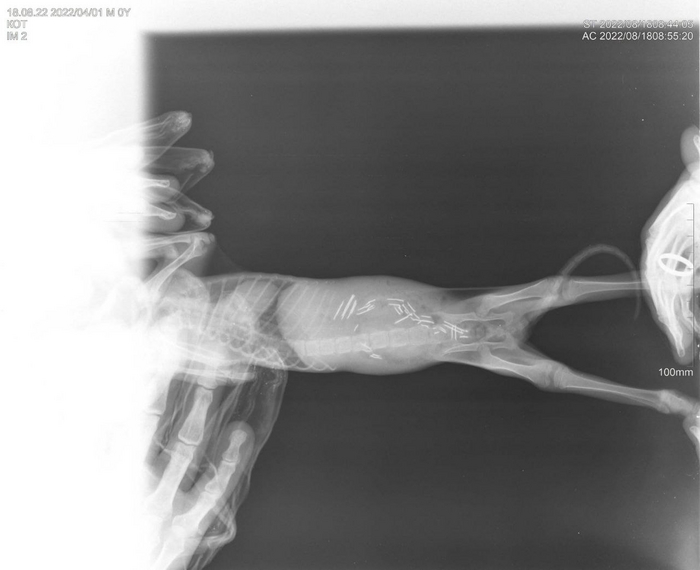

Напомним, что один из выпускников, это котик, у которого при поступлении были обнаружены гвозди в кишечнике. К счастью, обошлось без операции и без последствий для здоровья животного.